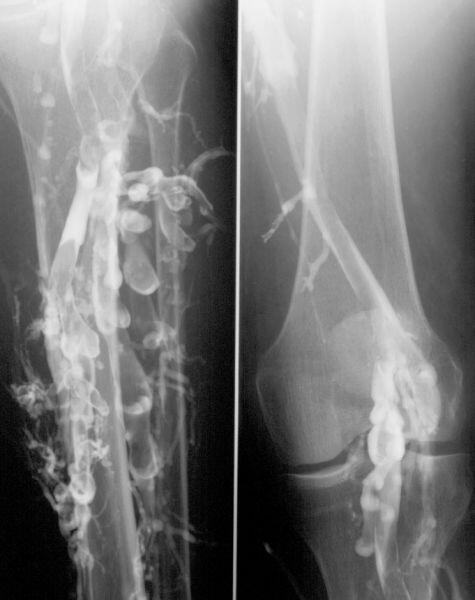

Phlébographie (exploration des veines) avec thrombose